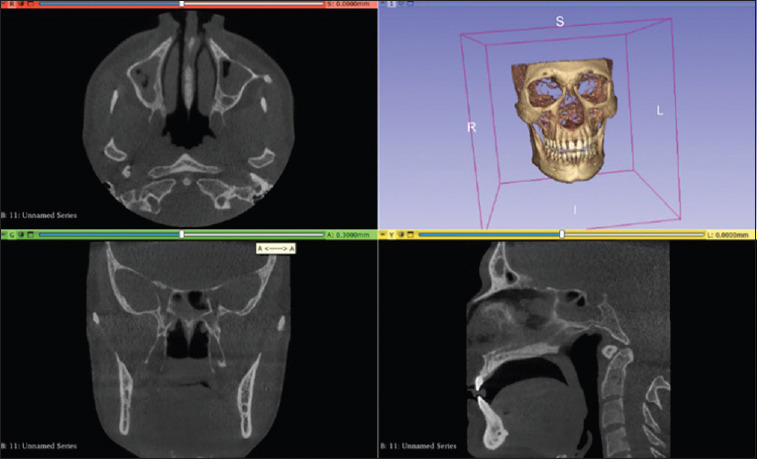

Materials and methods: Two cases diagnosed with chronic recurrent dislocation of TMJ were selected for the study. A three-dimensional virtual model was reconstructed from cone-beam computed tomography (CBCT) images of a patient. The AR visualisation was created by developing an Android app which superimposed the virtual model and the TMJ in real time. The skin puncture point was marked on the skin, and the needle was guided to the upper compartment of the joint using this superimposed view to perform TMJ arthrocentesis.